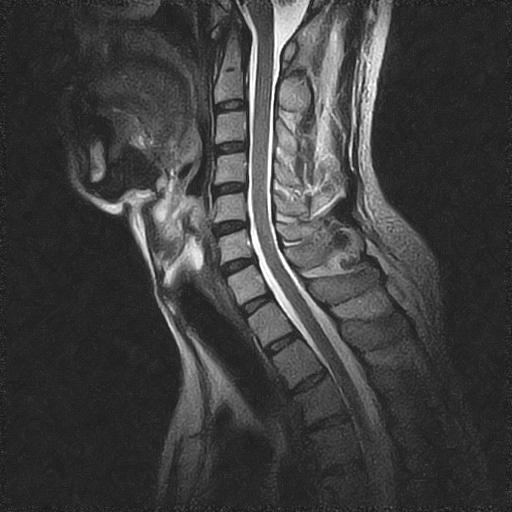

Sagittal T2 FSE with RADAR technology enables motion- and flow-free imaging..